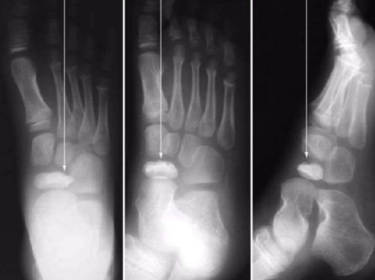

What is this? Where is it typically found? | Os interphalangeus. Typically found on the inferior aspect of the hallux IPJ. It is rare to see this ossicle at the IPJs of the lesser toes. |

What is this? | Accessory sesamoids. |

What is this? | Os Intermetatarseum |

What is this? | Tibialis Anterior Tendon Sesamoid |

What is this? | Os Vesalianium |

What is this? What tendon is it found in? | Os Peroneum. Sesamoid bone found in peroneus longus tendon. |

What is this? | Os Infranaviculare |

What is this? | Os Supranaviculare |

What is this? | Os Supratalare |

What is this? What type is it? | Accessory navicular (Os tibiale externum) Type 1: Sesamoid in the tendon |

What is this? What type is it? | Accessory navicular (Os tibiale externum) Type 2: Articulating accessory ossification centre |

What is this? What type is it? | Accessory navicular (Os tibiale externum) Type 3: Fused accessory ossification centre |